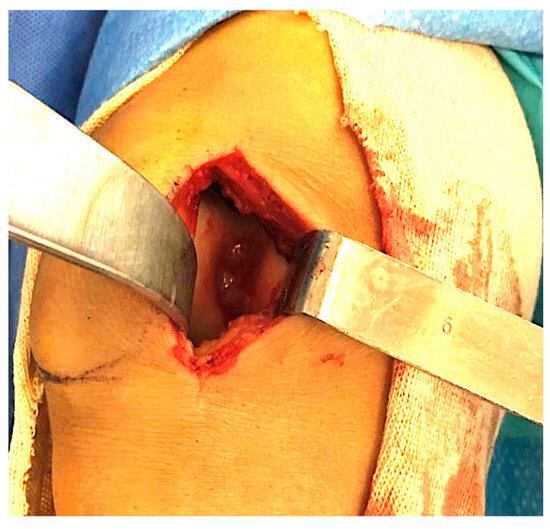

2.1. Surgical Procedure